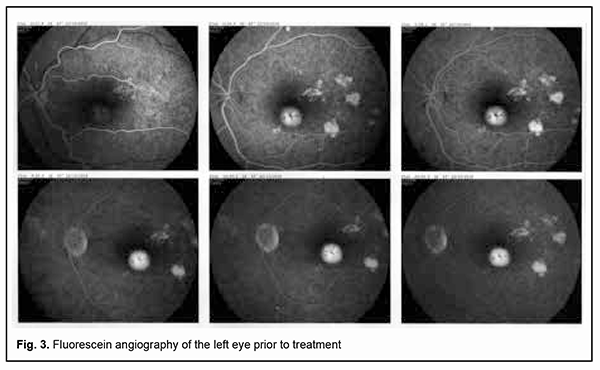

Fluorescein angiography (FA) revealed multiple leakage areas at the optic disc and along the course of the lower vascular plexus in the right eye (Fig. 2) and in the macula and paracentrally in the left eye (Fig. 3).

The patient was diagnosed with bilateral focal chorioretinitis. He underwent additional routine evaluation procedures to elucidate the etiology of the disease. His complete blood cell count, C-reactive protein, and rheumatoid factor were normal, and results of Mantoux test and Wassermann test negative. Evaluation by otorhinolaryngologist and dentist found no pathology. No DNA of Toxoplasma gondii, herpes simplex virus (HSV)-1 or HSV-2, or cytomegalovirus was found in the tear fluid. Tests for anti-Chlamydia trachomatis, anti-HSV-1, anti-HSV-2, anti-cytomegalovirus and anti-human immunodeficiency virus (HIV) by enzyme immunoassays were negative. Toxoplasma gondii IgG antibodies and Borrelia burgdorferi IgG antibodies were detected. The former antibodies were of low avidity. The patient was diagnosed with toxoplasmosis and borreliosis and prescribed a particular therapy by an infection specialist. He was treated on an inpatient basis at the eye hospital; particularly, he had retinal laser photocoagulation and a course of anti-inflammatory, anti-edematous, retinal protective and immunomodulating drug therapy. No positive changes were observed until the patient received his particular etiologic therapy. After the etiologic therapy for toxoplasmosis (oral trimethoprim-sulfamethoxazole, pyrimethamine and folic acid) and borreliosis (intramuscular ceftriaxone) was administered, complaints disappeared and patient’s visual functions recovered. Particularly, visual acuity improved to 1.0 OU, and the patient exhibited normal visual fields as assessed by perimetry. In addition, the retinal edema disappeared, and OCT as well as fluorescein angiography was normal for both eyes. Moreover, no worsening was observed throughout two years of follow-up. Discussion Since there are few reports in the literature describing the ocular manifestations of Lyme disease, borreliosis is infrequently suspected by ophthalmologists as an etiologic factor in the development of inflammatory eye disease. In addition, an enzyme immunoassay for Borrelia burgdorferi is not used in a routine diagnostic evaluation of patients with inflammatory eye disease. It has been reported that ocular manifestations develop in the presence of common symptoms of Lyme disease such as fever, joint pain and skin manifestations [3, 10]. It is of note that there were no extraocular manifestations of the disease in our patient. This case indicates that elucidating etiology and administering etiological therapy are essential for successful treatment outcomes. Conclusion Therefore, specific Borrelia burgdorferi antibody serology is required to elucidate the etiology of ocular inflammation if a patient has a history of tick bites even in the absence of symptoms of Lyme disease. One should take in account that ocular infections are frequently mixed in nature. Determining etiology and administering particular etiological therapy are essential for successful outcomes of treatment for infectious disease.